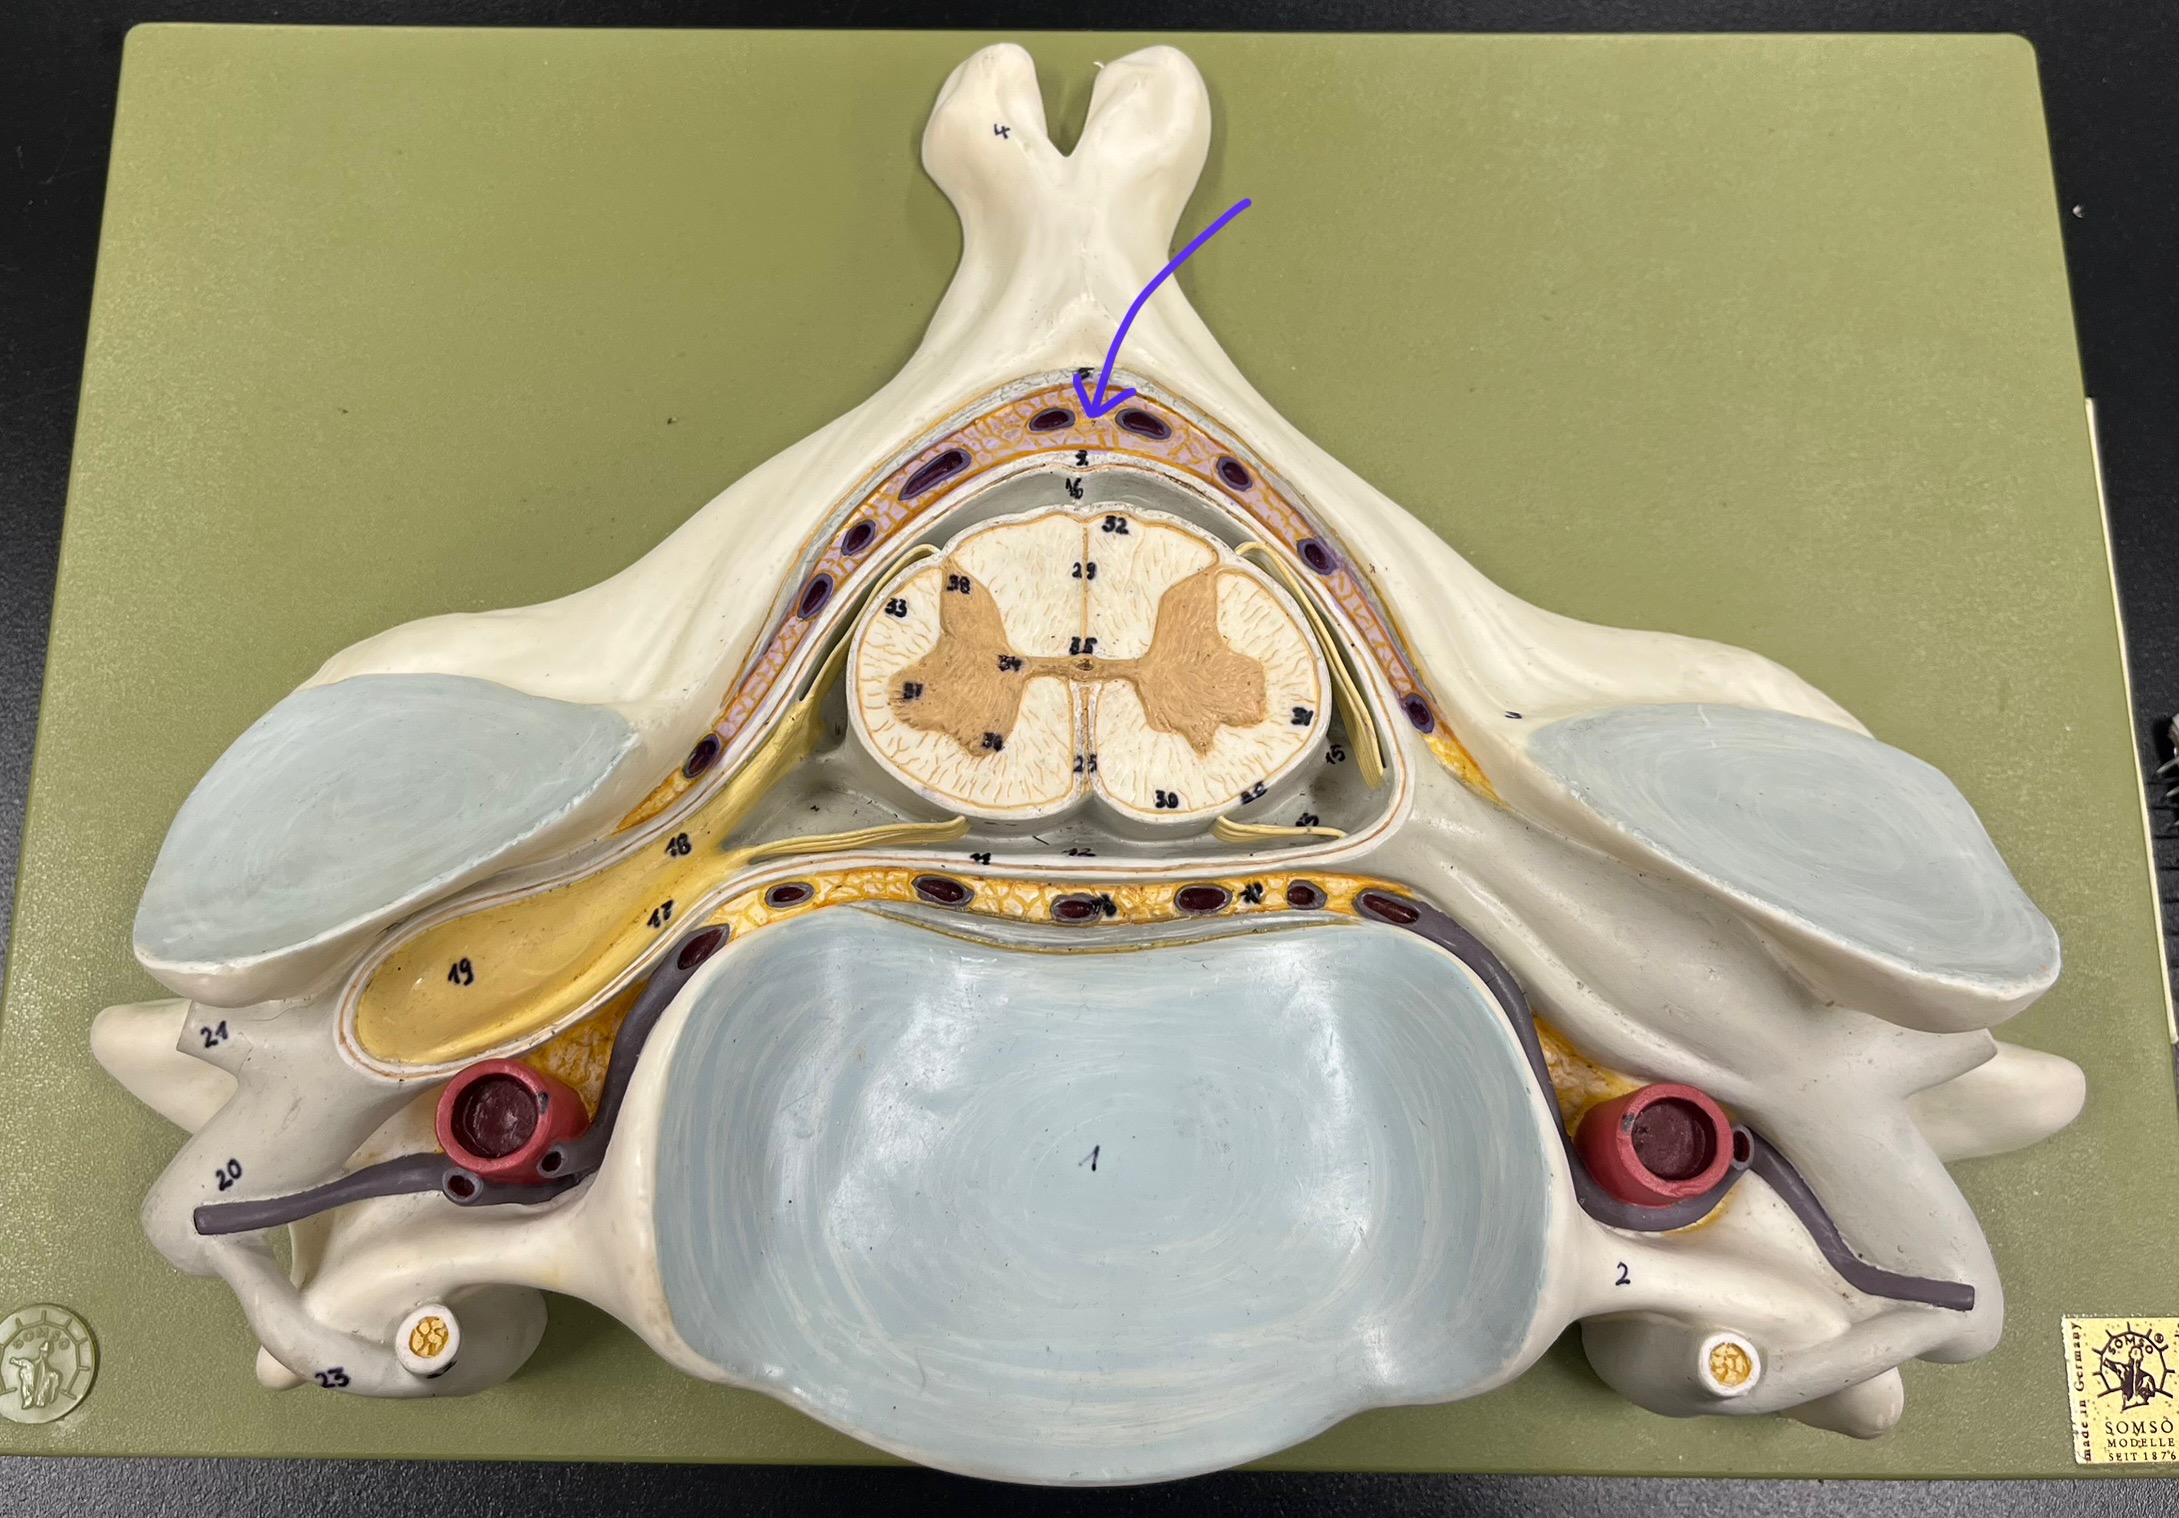

epidural space

dura mater

subdural space

arachnoid mater

subarachnoid space

pia mater

denticulate ligaments

What is the groove here?

anterior median fissure

posterior median sulcus

posterior (dorsal) horn

posterior (dorsal) horn; R—>L

anterior (ventral) horn

lateral horn (selected models)

gray commissure

central canal

anterior column

lateral column

posterior column

white commissure

posterior (dorsal) root ganglion

What is the bulb here?

posterior (dorsal) root ganglion

posterior (dorsal) root

posterior (dorsal) root

anterior (ventral) root

anterior (ventral) root

dorsal ramus

dorsal ramus

ventral ramus

ventral ramus

rami communicantes

rami communicantes

sympathetic chain ganglia

sympathetic chain ganglia